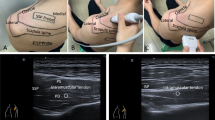

EUS includes different techniques (Fig. 1): Strain or compression elastography (SE) evaluates the elasticity of the underlying tissue by measuring the degree of deformation. Compression is applied manually or through physiological movements (breathing, vessel pulsation). This enables a semi-quantitative measurement of the tissue elasticity, as the elasticity is estimated by comparing the strain in the target tissue with strain of the surrounding tissue. Due to the manual applied pressure this technique has been shown to be operator depending [1, 3].

Experimental setting. The ultrasound probe was placed in an oblique sagittal position (a). The largest diameter of the supraspinatus muscles was detected using b-mode ultrasound (b). SWE measurement was performed at this location in a parallel orientation of the transducer to the muscle fibers (c). The velocity of shear wave propagation was measured at 10–15 points in the ROI. The measurement was repeated 5 times to cover almost the whole cross section area of the muscle. To ensure spectroscopic measurement at the same location the point of measurement was marked with a MRI visible gel capsule fixed to the patient’s skin

Shear wave elastography (SWE) was introduced by Sarvazyan et al. in 1998. A radiation force of a focused ultrasonic push pulse (duration approximately 320 μs) is used to induce a tissue oscillation of up to 20 μm. These so-called shear-waves move transversally to the direction of the ultrasonic waves. The shear wave velocity (SWV) depends on the elasticity of the examined tissue [26]. Using tracking beams of the transducer (acoustic radiation force impulse, ARFI) the propagation velocity of the shear-waves can be measured. This method is propagated as an objective and reproducible quantification of the tissue elasticity which is in contrast to SE not depending from the manual compression by the observer (Fig. 2) [26]. However, as it is an ultrasound technique with manual application of the transducer it may be susceptible for observer dependent bias.

Experimental studies showed that SWE is capable of measuring muscle stiffness in the supraspinatus muscle and may detect regions of different elasticity in the muscle, without focusing on FD. These preliminary studies showed that the orientation of the ultrasound probe needs to be parallel to the muscle fibers to achieve reliable results for the tissue stiffness with SWE [4, 15].

Forty-two patients with history of rotator cuff tear were included in this study. Mean age of the patients was 58.8 ± 7,65 years (range from 40 to 76). Thirteen were female and 29 were male patients. Twenty-eight underwent rotator cuff repair, the time after surgery was 2.3 years (± 0.7). The other patients had a history of rotator cuff tear but were treated conservatively. Patients’ clinical features are shown in Table 1. The maximum diameter of the supraspinatus muscle was detected using conventional ultrasound (b-mode) and this area was marked using a gel capsule (Fig. 3). After detection of this area a shear wave ultra-sound measurement (SWE) of the supraspinatus muscle was performed with a Siemens Acuson S3000 ultrasound system (Siemens AG, Munich, Germany) using a linear transducer (10mHz) the SWV was assessed with the software of the ultrasound device (virtual touch tissue imaging quantification [VTIQ], Siemens Medical Solutions, Siemens AG, Munich, Germany). Tissue elasticity was measured by aligning the transducer parallel to the muscle fibers at the largest diameter of the supraspinatus muscle (Fig. 1). As the process of manually selecting data via the ultrasound system’s console has the potential to significantly introduce bias SWE was performed by one blinded radiologist (DK). The shear wave velocity (m/s) was measured at 10–15 points in the manually placed region of interest in 5 pictures trying to fully cover the muscles cross section. The forearm of the patients was placed on an armrest to avoid muscle contraction during the examination .